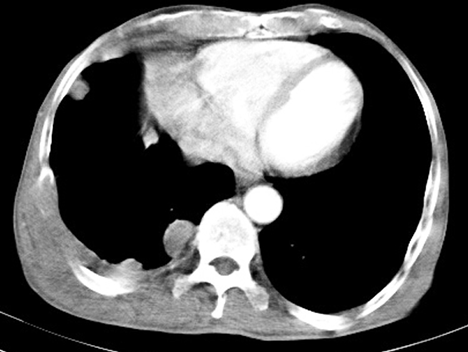

胸膜恶性肿瘤考虑转移瘤

胸膜恶性间皮瘤